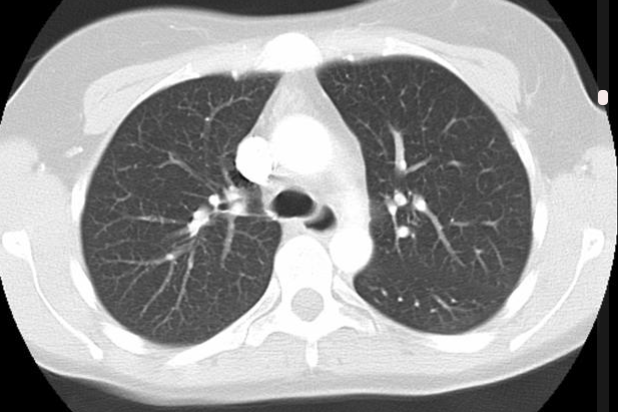

The CD Lab Machine Learning Driven Precision Imaging  (Start 2021) develops machine learning models for the prediciton of individual disease course and treatment response in lung cancer patients. It explores methodology, medicine and the legal aspects of using AI in clinical care. It is funded by the Christian Doppler Gesellschaft.

more